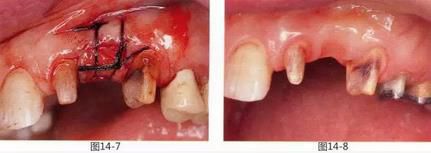

圖13-10  取模前正面照。獲得了足夠量的附著齦。

圖13-11  取模前咬合面照。獲得了左右對稱的牙槽嵴形態(tài)。